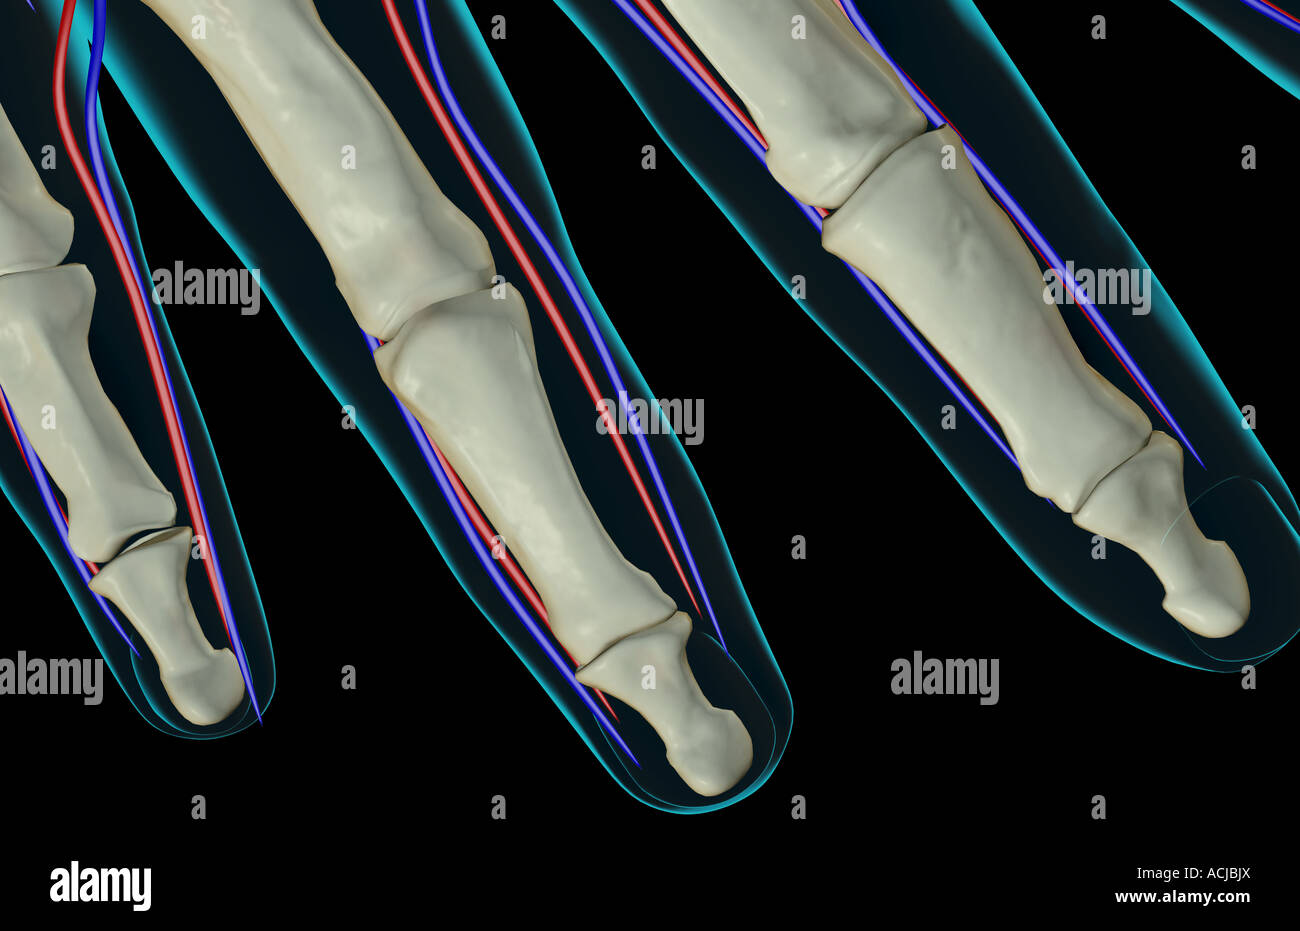

The blood supply of the fingers Stock Photohttps://www.alamy.com/image-license-details/?v=1https://www.alamy.com/stock-photo-the-blood-supply-of-the-fingers-13168849.html

The blood supply of the fingers Stock Photohttps://www.alamy.com/image-license-details/?v=1https://www.alamy.com/stock-photo-the-blood-supply-of-the-fingers-13168849.htmlRFACJBJX–The blood supply of the fingers